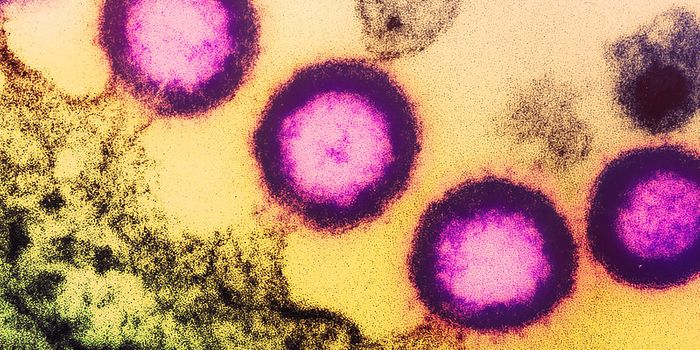

FEB 03, 2025MicrobiologyThe highly pathogenic avian influenza H5N1 infection has killed millions of birds around the world, and has spread to hu ...

JAN 05, 2025MicrobiologyThis story, like the virus it is about, continues to evolve. This article summarizes some of the recent findings and opi ...